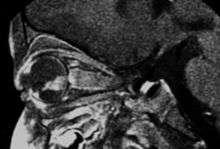

Aspect of trilateral retinoblastoma on MRI